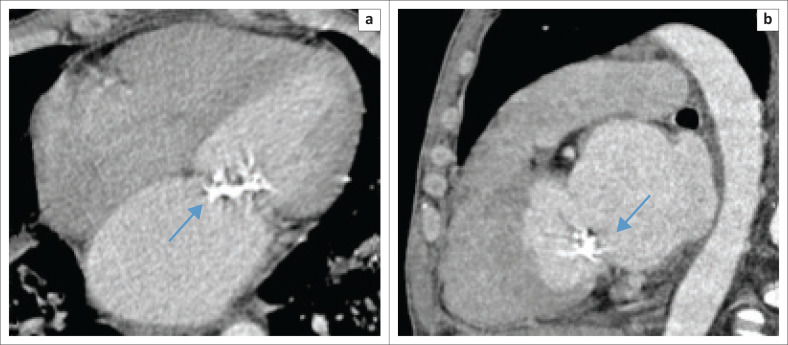

背景:国际文献报道艾滋病毒感染者(PLWH)心血管疾病患病率增加,推断其与冠状动脉粥样硬化和斑块形成加速有关。很少有当地的hiv相关心脏病研究证实了这一点。心脏斑块的早期识别将有助于临床医生进行风险分层和实施治疗策略,以降低发病率和死亡率。在资源有限的情况下,使用传统的计算机断层扫描(CT)可能在识别高危个体方面发挥作用。目的:本假设生成研究旨在通过评估心脏钙化来确定HIV对加速血管老化的贡献,在年轻HIV阳性人群中,常规CT胸部成像偶然检测到心脏钙化。方法:回顾性定量分析在夸祖鲁-纳塔尔省一家三级医院,南非,超过5年的时间。年轻患者(18-45岁)接受了不同适应症的CT胸部成像,并根据免疫状态、钙化的存在、不存在和位置进一步分类。排除艾滋病毒感染状况不明的患者。结果:心脏钙化的可能性随着年龄的增长而增加,与HIV状态无关。在队列之间没有统计学上的显著差异。在预对比子类别中,较低的p值表明“迫在眉睫”的统计显著性。造影剂可能掩盖了一些钙化。由于未能记录大量患者的免疫状态,导致他们被排除在外,限制了研究。结论:年轻hiv感染者中偶然发现的心脏钙化的患病率增加值得进一步评估和心血管风险分层。

Objectives: This hypothesis-generating study was aimed at determining the contribution of HIV to accelerated vascular aging by assessing cardiac calcifications, incidentally detected on conventional CT chest imaging, in a young HIV-positive population.

Method: A retrospective quantitative analysis was performed at a tertiary hospital in KwaZulu-Natal, South Africa, over a 5-year period. Young patients (18-45 years) who underwent CT chest imaging for varied indications were included, further sub-categorised by immune status, the presence, absence and location of calcifications. Patients with unknown HIV statuses were excluded.

Results: An increased probability of cardiac calcification with increasing age, independent of the HIV status, was established. No statistically significant difference could be demonstrated between the cohorts. In the pre-contrasted subcategory, a lower P-value suggested an 'imminent' statistical significance. Contrast may have obscured some calcifications. The failure to record the immune status in a large number of patients resulted in their exclusion and limited the study.